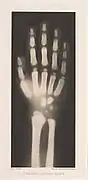

Le chimiste contribue à la photographie par des articles co-écrits avec Josef Maria Eder sur les spectres des éléments chimiques. En 1894, il publie un livre sur la photographie interférentielle de Gabriel Lippmann et les améliorations qu'il y apporte. Il travaille dans le domaine des rayons X. Puis Valenta développe les premiers rayons X stéréo et publie un livre sur les papiers d'impression. Ses autres travaux comprennent l'utilisation du rouge de glycine et du violet d'éthyle comme colorants sensibilisants (1898-1899) ; l'analyse spectrale de centaines de colorants à l'aniline et de leur aptitude à filtrer la lumière et à imprimer des encres et des recherches sur la reproduction photomécanique[2].

• 1896 : Versuche über Photographie mittelst der röntgen'schen Strahlen avec Josef Maria Eder[3].